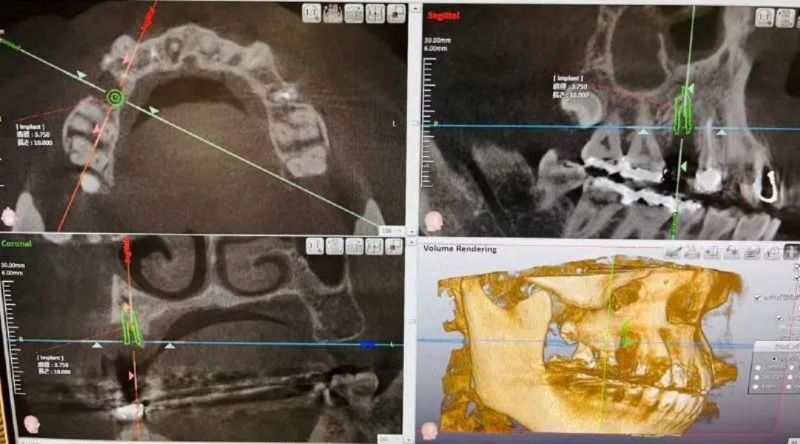

治療に関しては 新しいCTなどの設備なども用意されており院長先生が一貫して治療を行っているため、担当が変わる心配もなく、信頼関係を築くことができ、安心して治療をお任せできる歯科医院をお探しの方は、吉澤歯科クリニックへ足を運んでみてはいかがでしょうか。